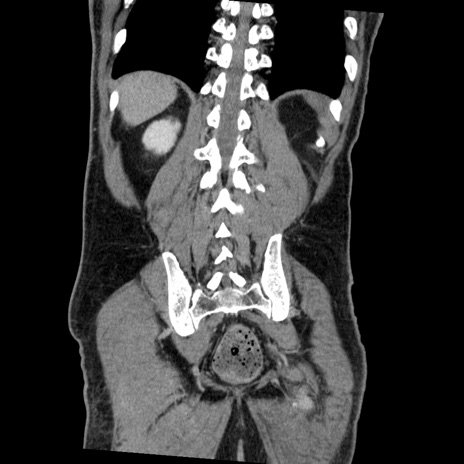

症例22(冠状断像)

【症例】50歳代男性

【主訴】腹痛

【現病歴】AVMからの被殻出血のため回復期リハ病棟入院中。 本日午後3時頃急に下腹部痛が出現した。

【既往歴】AVM、被殻出血、虫垂炎、高血圧

【身体所見】意識晴明、左半身不全麻痺、会話の理解は良好、36.5°C、腹部:膨隆、全体に板状硬、下腹部正中に圧痛点あり、反跳痛-、筋性防御不明、右下腹部にope scar

【データ】WBC 9400、CRP 0.06